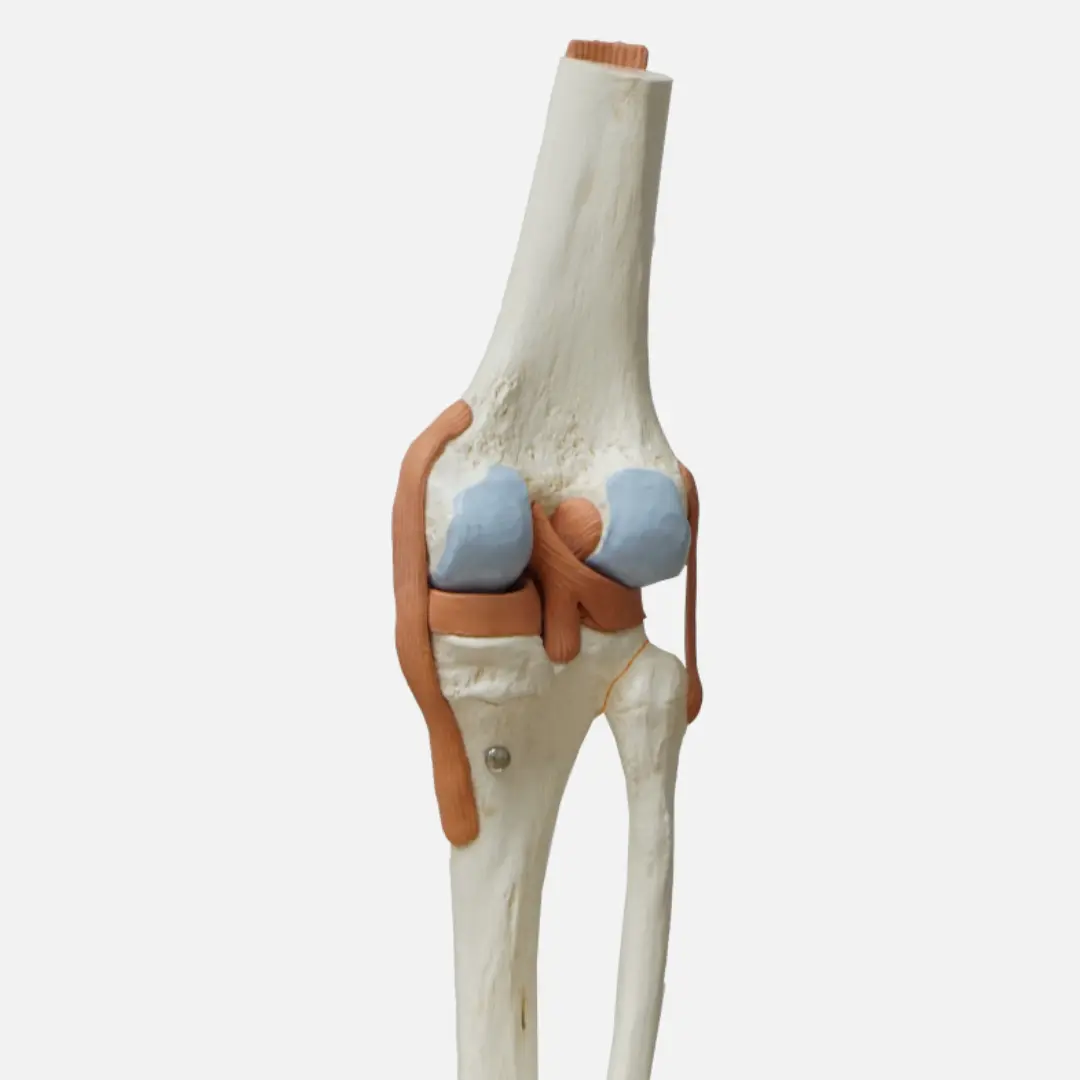

퇴행성관절염은 관절을 보호하고 움직임을 원활하게 하는 연골이 점진적으로 손상되거나 퇴행성 변화를 겪으면서 발생하는 만성 질환이에요. 연골은 뼈와 뼈 사이에서 충격을 흡수하고 마찰을 줄여주는 쿠션 역할을 하는데요. 나이가 들거나 과도한 사용, 외상 등으로 연골이 닳아 없어지면 뼈와 뼈가 직접 부딪히면서 염증과 통증을 유발하게 됩니다.

퇴행성관절염은 주로 무릎, 엉덩이(고관절), 척추, 손가락 끝마디 등 체중을 지탱하거나 많이 사용하는 관절 부위에 잘 발생해요. 관절염의 종류 중 가장 흔한 형태이며, 유전적 요인, 비만, 과도한 운동, 과거 관절 손상 등이 복합적으로 작용하여 발병합니다. 단순히 노화 현상으로만 볼 것이 아니라, 적극적인 관리와 치료가 필요한 질환이에요. 연골이 한번 손상되면 자연적으로 재생되기 어렵기 때문에, 초기에 증상을 인지하고 진행을 늦추는 것이 중요하답니다.